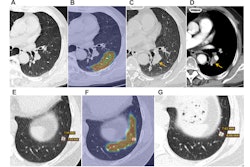

Representative axial images of mild, moderate, and severe emphysema at baseline low-dose CT (LDCT). Participants were categorized as having no emphysema or mild, moderate, or severe emphysema. When present, emphysema was mild if no distinct regions of reduced attenuation were visible on the CT scan, but vascular splaying indicates parenchymal expansion, or if only occasional discrete low-attenuation regions were observed. Moderate emphysema was defined by the presence of identifiable low-attenuation regions affecting less than half of the lung parenchyma, whereas severe emphysema was defined by the presence of identifiable low-attenuation regions that involved more than half of the lung parenchyma. A scoring system from 0 to 3 was applied, corresponding to none, mild, moderate, and severe emphysema, respectively. Yellow circle indicates the extent of emphysema. (A) A 67-year-old man with mild emphysema at baseline LDCT in 2002. Baseline LDCT scan shows vascular splaying, suggesting parenchymal expansion due to emphysema and occasional discrete low-attenuation regions. The participant ultimately died of cardiovascular disease 15.4 years (184.2 months) later. (B) A 69-year-old man with moderate emphysema at baseline LDCT in 2007. The participant died of cardiovascular disease 1.8 years (21.9 months) later. Identifiable low-attenuation regions affected less than half of the lung parenchyma. (C) An 85-year-old woman with severe emphysema at baseline LDCT in 2006. After 5.5 years (65.5 months) of follow-up, the participant died due to chronic obstructive pulmonary disease–related causes. Identifiable low-attenuation regions involved more than half of the lung parenchyma.Image and caption courtesy of the RSNA.